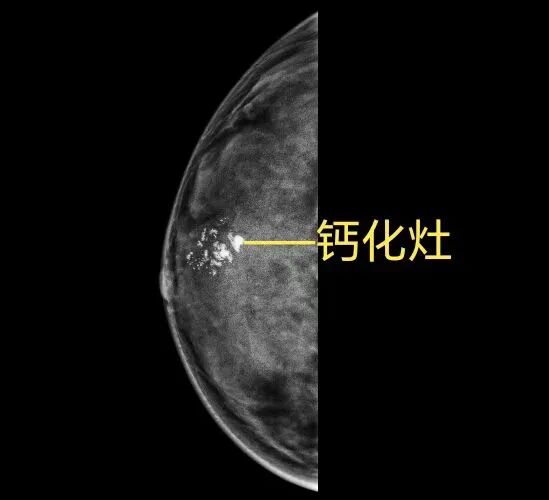

但是超声对细小钙化灶的探查不及钼靶,特别是对于大乳房和脂肪型乳房,也就是说:乳腺B超对细小钙化的判断不够准确!而这恰恰就是乳腺钼靶的优点。

乳腺钼靶的优势在于它对钙化灶极度敏感,而多数乳腺癌具有特征性钙化表现,特别对于以少许微小钙化为唯一表现的早期乳腺癌,只有凭借钼靶检查才能被早期发现和诊断。

临床工作中我们也确确实实见过乳腺B超和磁共振(MRI)检查均无异常,乳腺钼靶检查却发现了细小簇状钙化,最终手术切除病理检查证实为乳腺原位癌的患者。

可以简单地理解为:钼靶检查“看”钙化灶比较强,而B超“看”小肿块比较强。